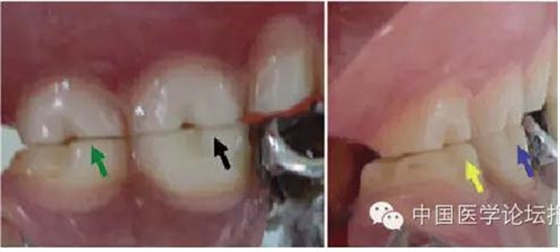

這種咬合接觸的結(jié)果是局部的咬合力集中在凸點(diǎn)接觸的位置,不能被有效分散,可造成受力部位牙體、牙周組織的應(yīng)力集中。最常見的表現(xiàn)是后牙頰舌向呈對(duì)刃關(guān)系,另外還常見于不完全遠(yuǎn)中關(guān)系或不完全近中關(guān)系的情況,此時(shí)從近遠(yuǎn)中方向來(lái)看,上下后牙牙尖之間凸凸相對(duì)(圖3)。

圖3 后牙凹凸接觸關(guān)系